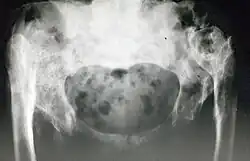

Die dysplasiebedingte Hüftluxation bei Erwachsenen ist eine (unbehandelte) Hypoplasie mit sekundärer Luxation des Hüftgelenks. Der Femurkopf steht nicht im Acetabulum, sondern darüber am Darmbein. Im angelsächsischen Sprachgebrauch wird die Situation als neglected congenital dislocation of the hip bezeichnet – wobei „dislocation“ eigentlich so falsch ist wie „Luxation“.

Zur Diagnose reicht eine Röntgenaufnahme des Beckens. Der radiologische Befund sollte weder mit dem Proximalen Femurdefekt noch mit der (extrem seltenen) teratologischen Luxation verwechselt werden.